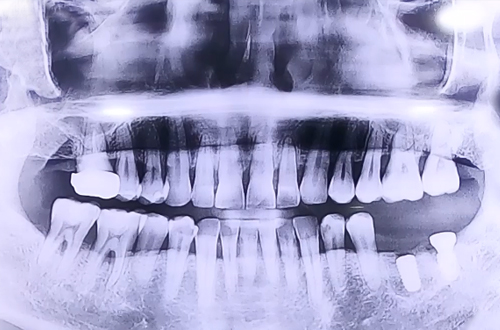

BEFORE

맨 앞쪽 발치 후 오랜 기간이 지난 큰 어금니와 앞쪽으로 기울여져 있으며 염증이 심한 사랑니,

그로 인해 심한 충치와 염증으로 흔들림이 많았던 사랑니 앞쪽 어금니로 자연 식립과 즉시 식립이 동시에 이루어진 환자분이십니다.

맨 앞쪽에 발치 후 오랜 기간이 지난 큰 어금니 부위에는 자연 식립 임플란트를 진행해 드렸고

사랑니와 그로 인해 흔들림이 심했던 큰 어금니를 둘 다 발치한 뒤에 원래 있어야 하는 자리에

뼈이식과 임플란트를 동시에 진행하며 반듯하게 심어 뚜껑을 덮어 마무리해 드렸습니다.